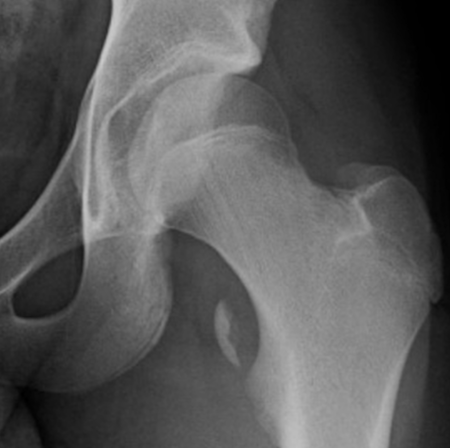

This two-hour postgraduate lecture provides an advanced, clinically relevant approach to hip orthopedic assessment for chiropractic physicians. Emphasis is placed on applied anatomy, pain generators, orthopedic examination strategies, and imaging indications that improve diagnostic accuracy and risk stratification. Through case-based discussion and imaging correlation, attendees will strengthen their ability to differentiate hip pathology from lumbar, pelvic, and systemic conditions while improving clinical decision-making and referral appropriateness.

- MRI and advanced imaging correlation

- Differential diagnosis: hip vs. lumbar vs. pelvic pathology

- Overview of imaging strategies (acute vs. chronic hip pain